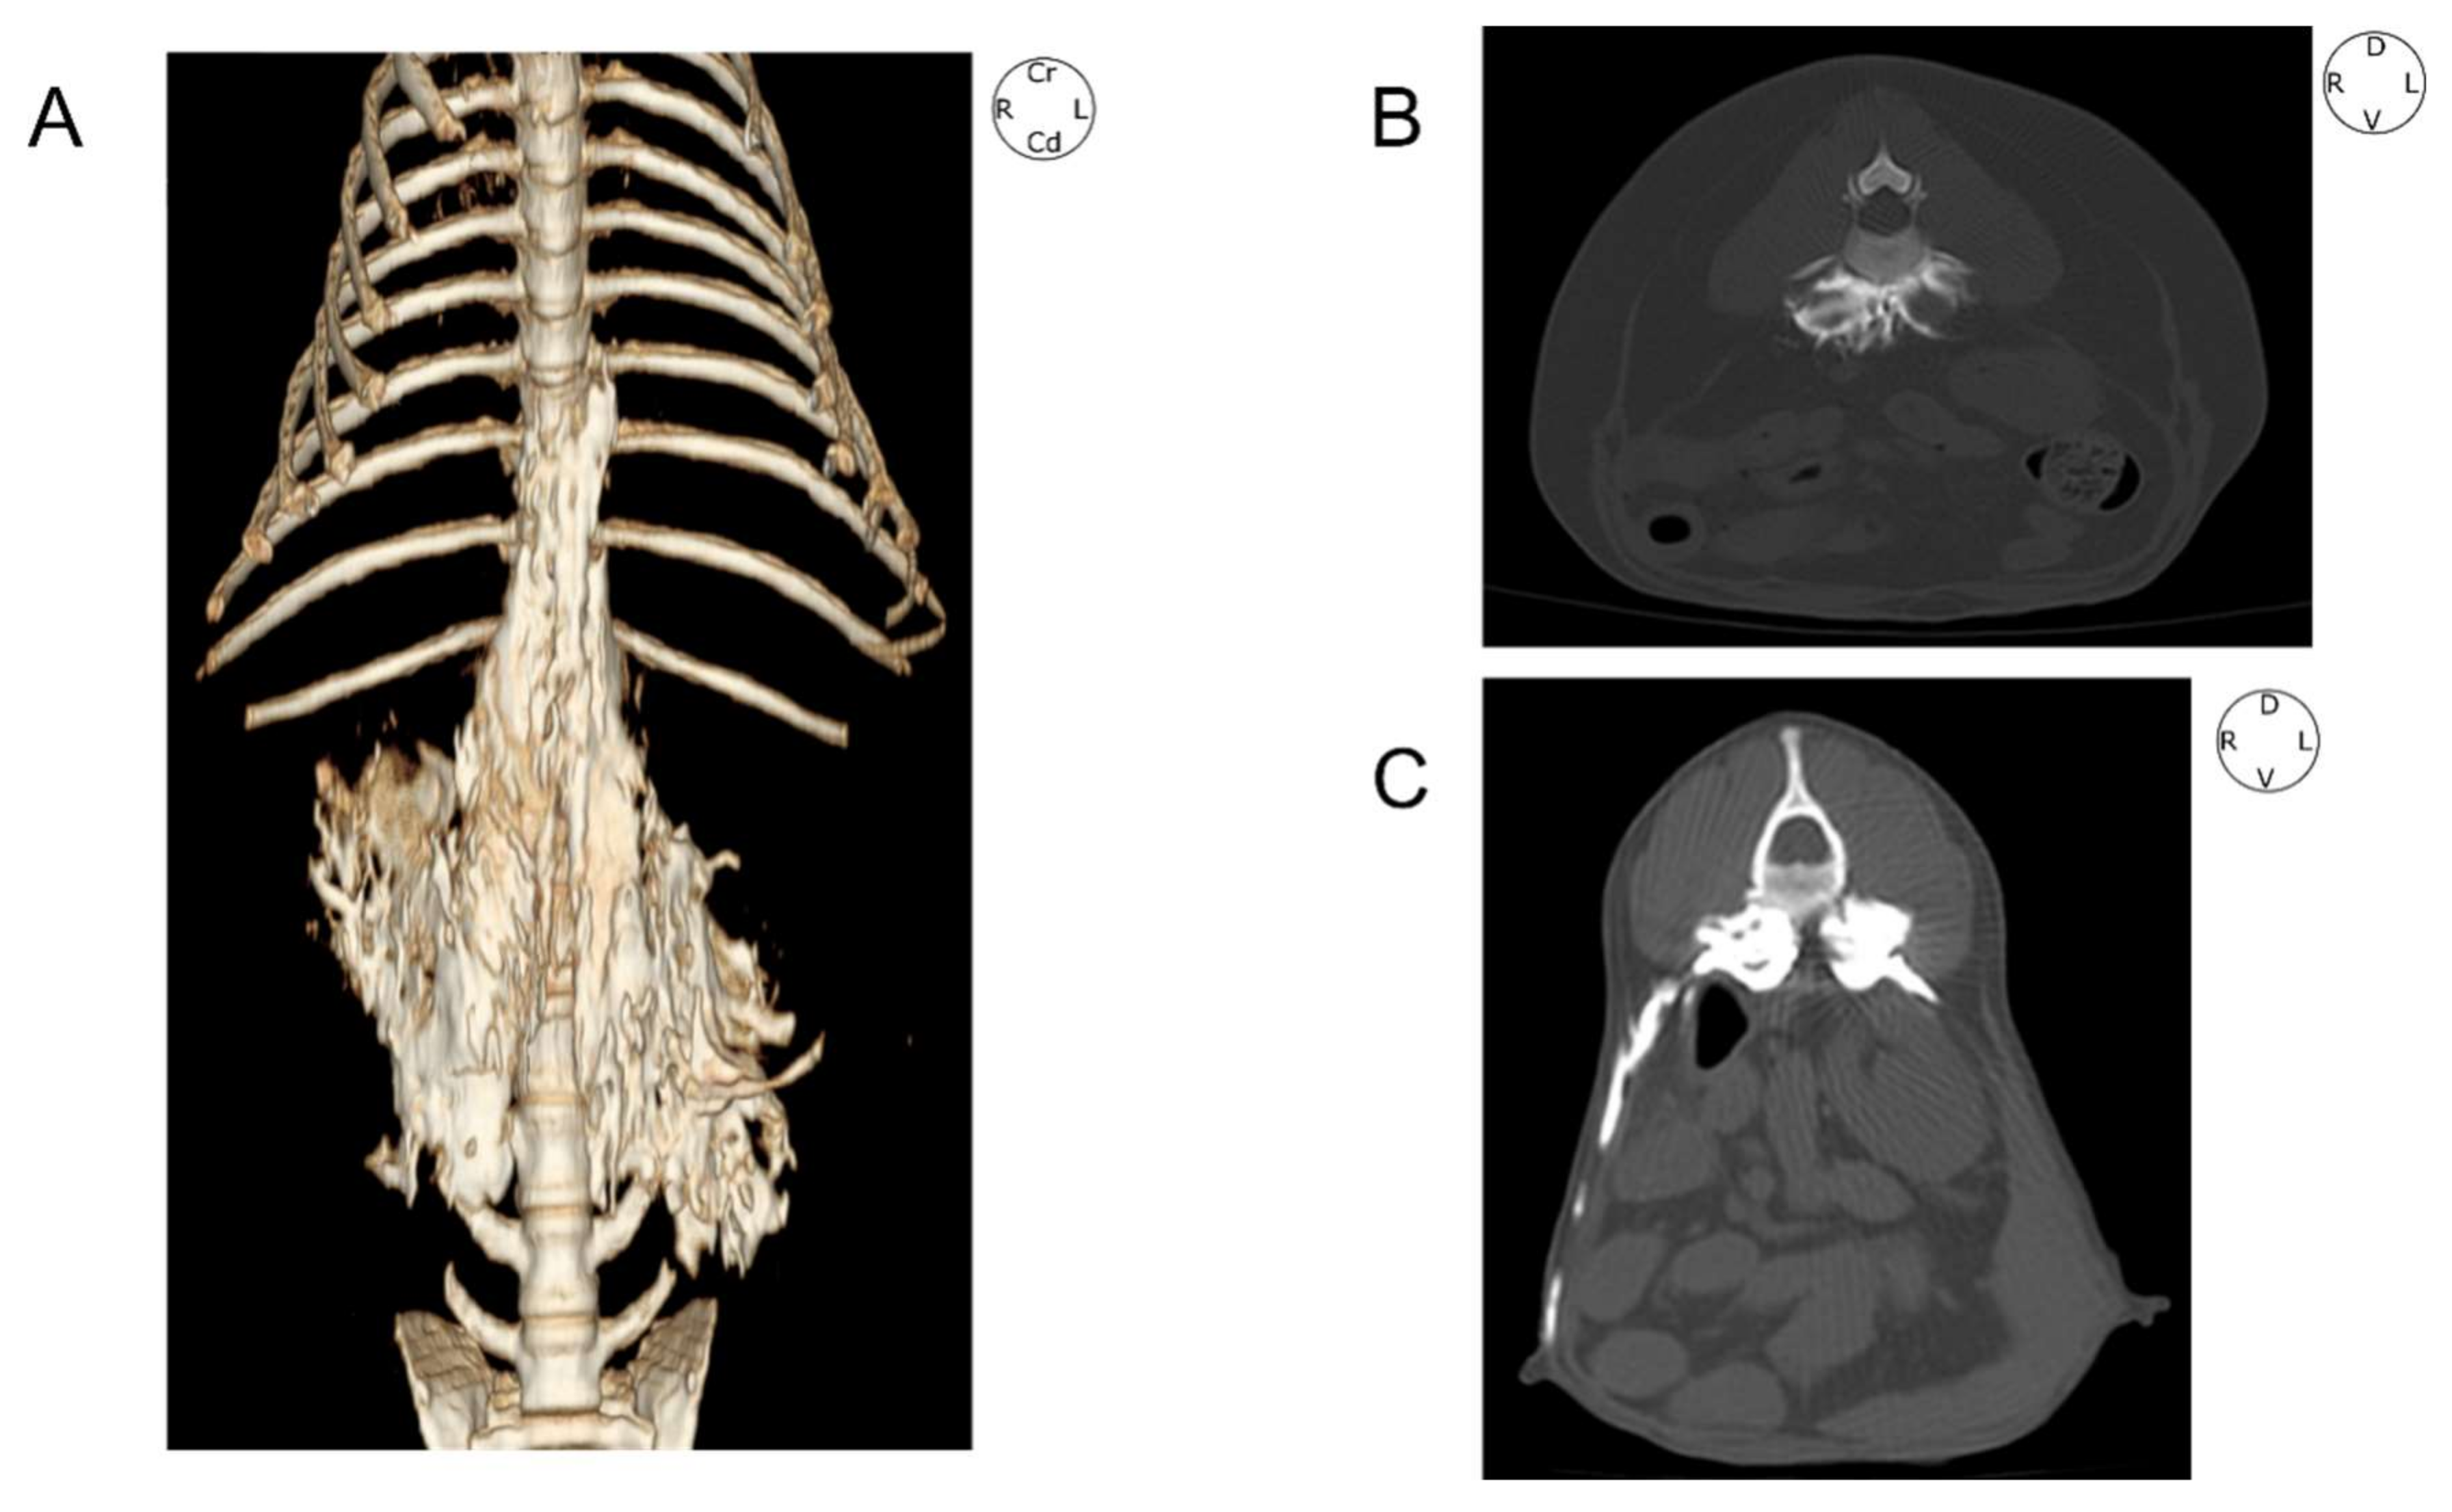

3.3. Tomographic Study

3.5. Cross-Section Study